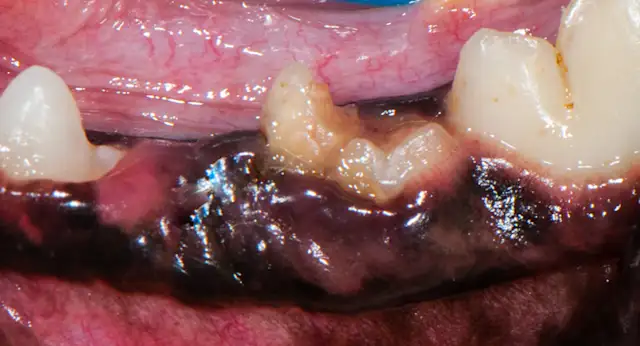

Left mandibular cheek teeth.